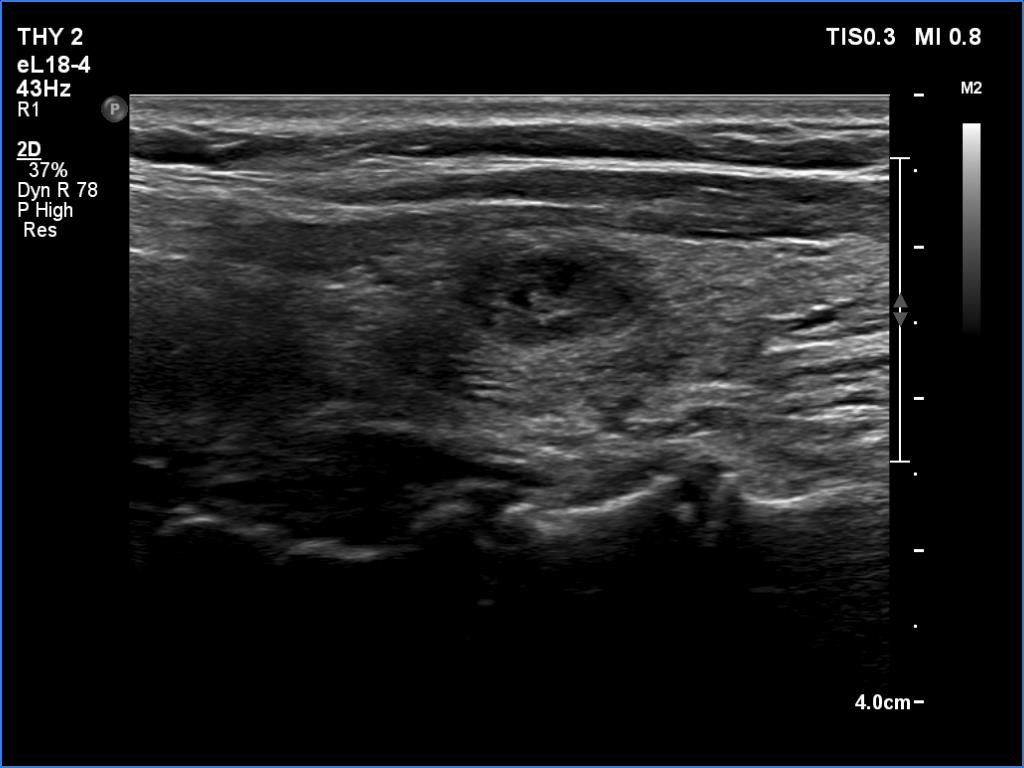

Examination a year after the first visit (third row of images):

Clinical presentation: The patient had no complaints.

Palpation: no abnormality.

Laboratory tests: TSH 2.05 mIU/L, FT4 13.7 pM/L.

Ultrasonography: The ultrasound pattern has normalized. There was a moderately hypoechoic nodule in the right lobe while a cystic lesion in the left one.

Cytology of the right nodule resulted in benign colloid goiter.

Suggestion. Follow-up in two years.